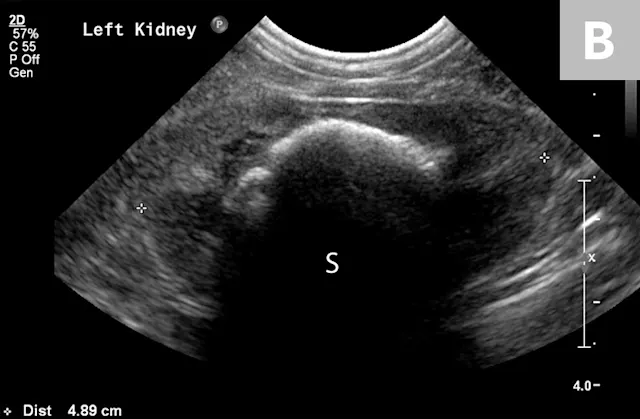

Clinical signs associated with ureteral calculi may range from chronic non-specific signs to acute or chronic renal failure. The presence of hydronephrosis can be highly suggestive of a ureteral obstruction (Figure 6).

FIGURE 6A

1 / 2

Mild to moderate right hydronephrosis and proximal ureteral dilation in a Dalmatian.